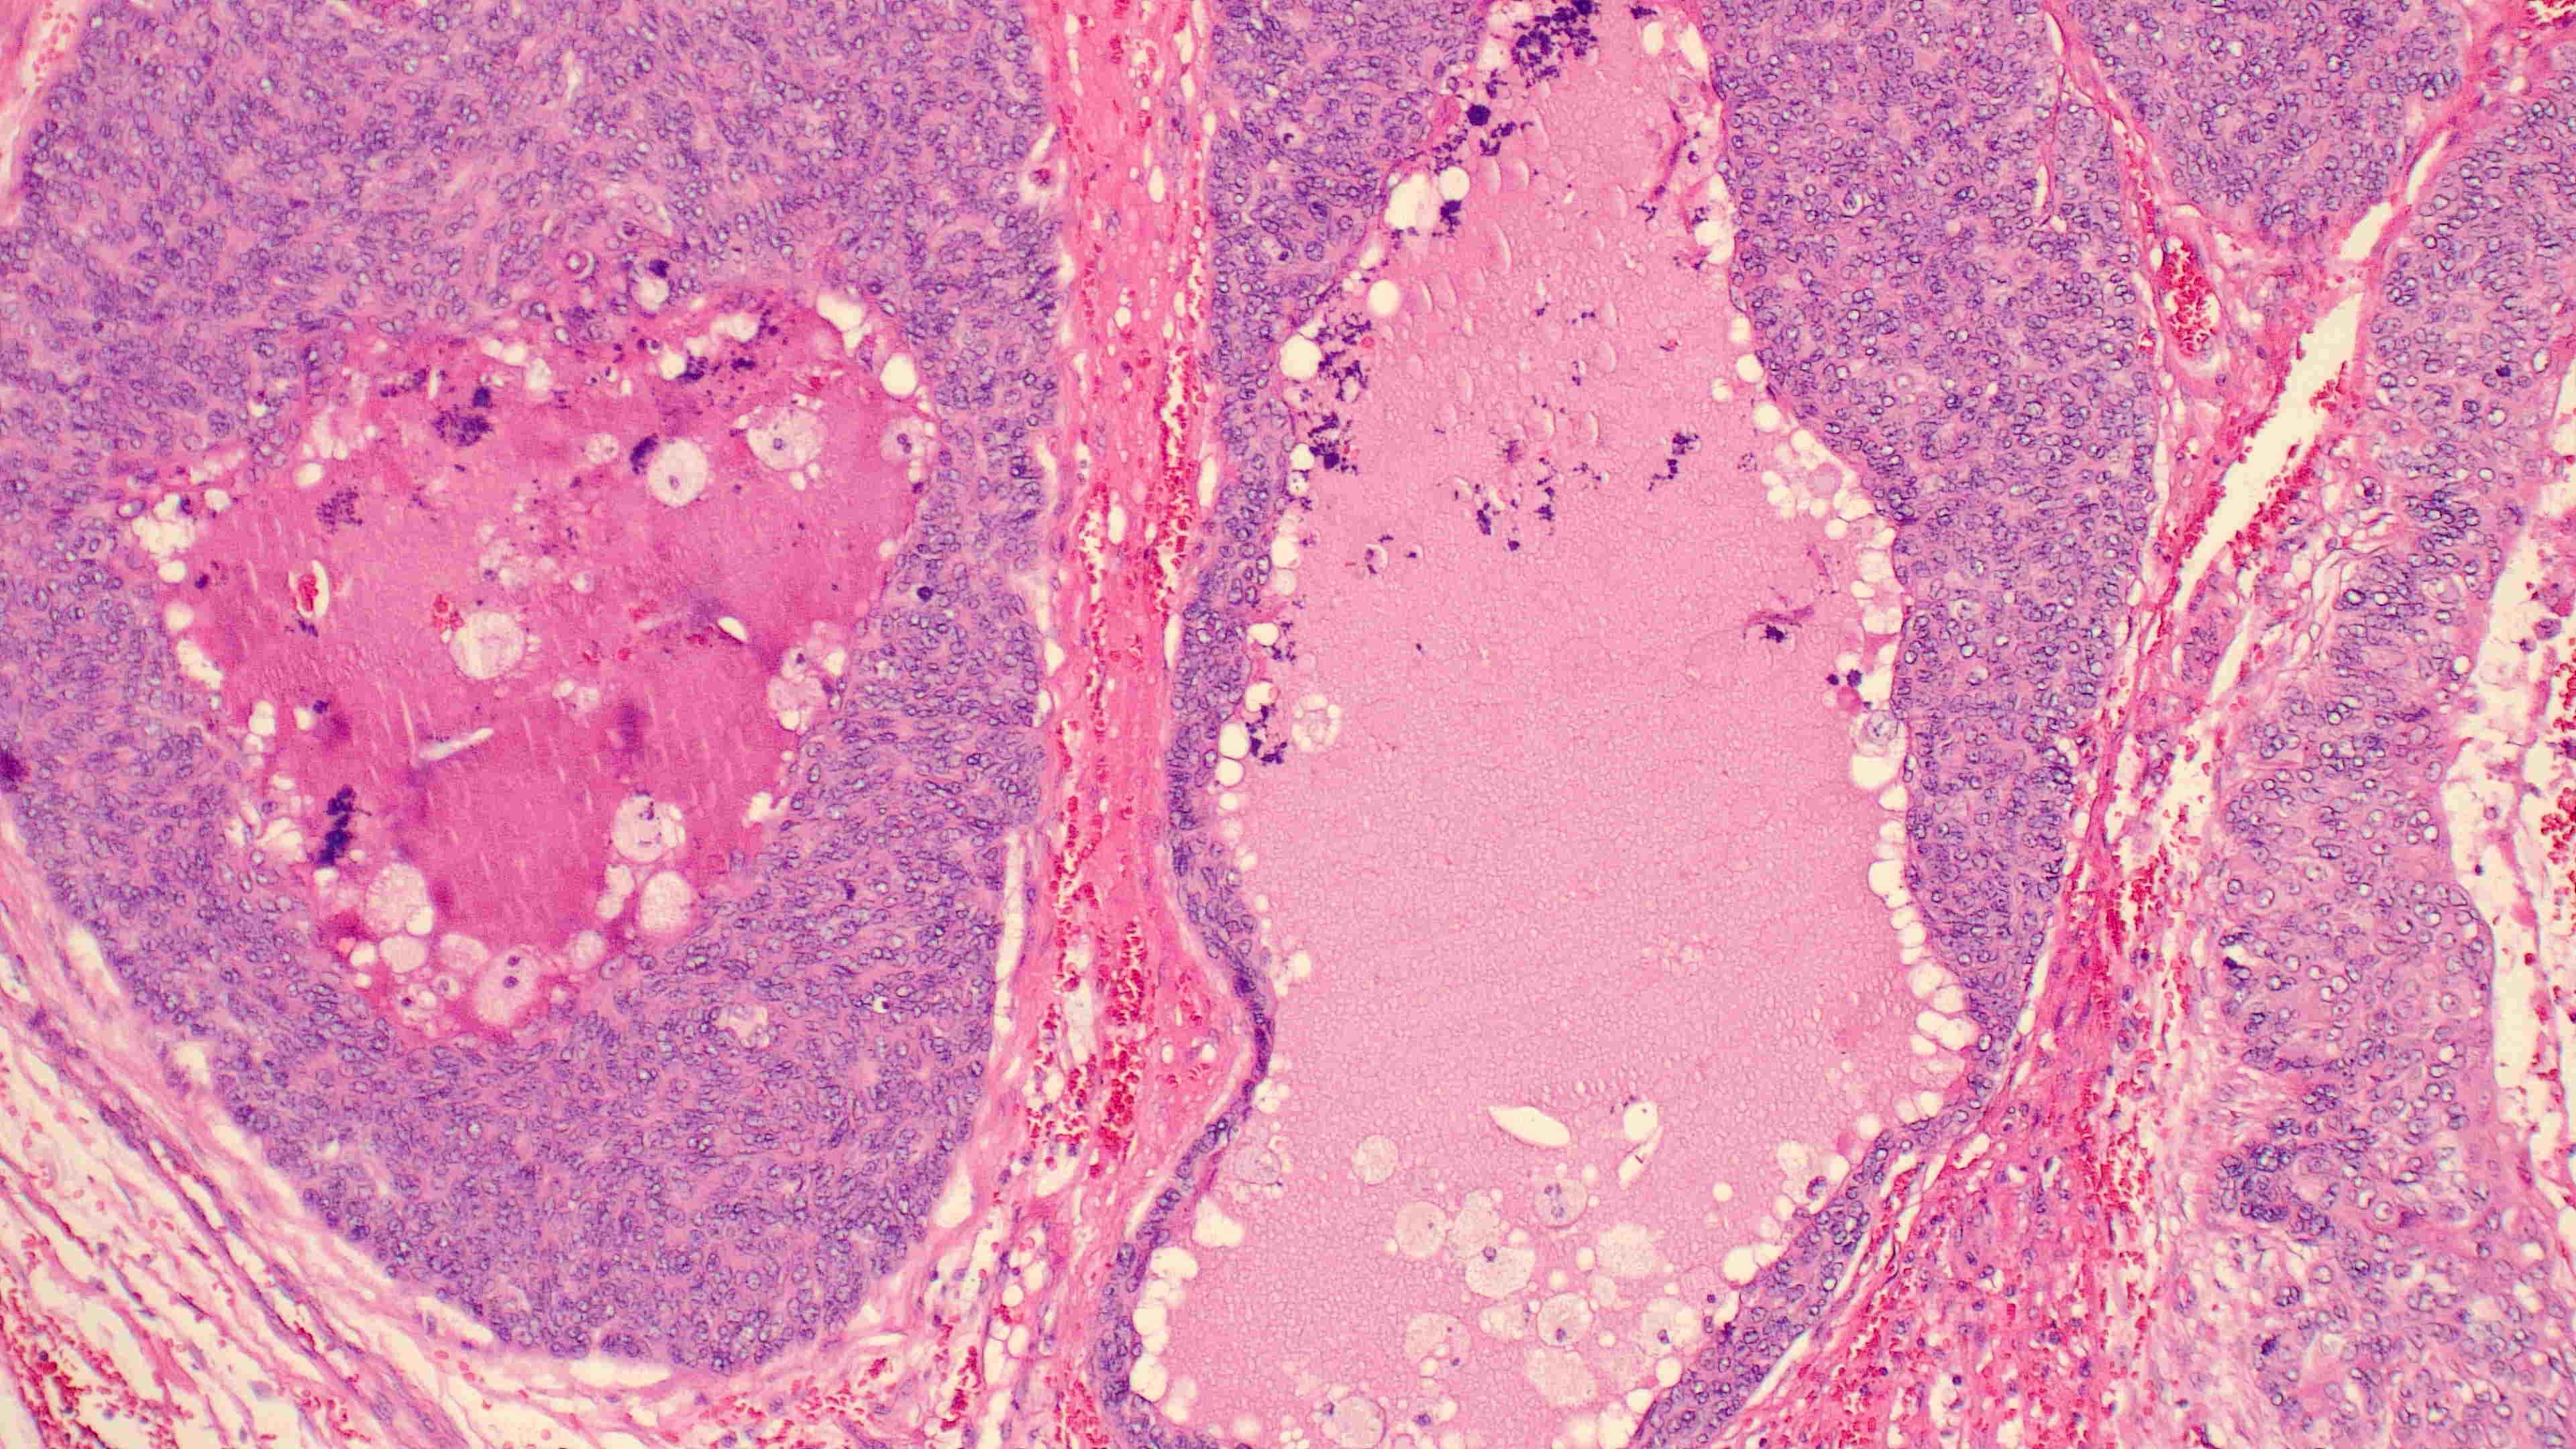

下巴肿物

带皮不规则组织3*3*2cm,切面灰白灰褐实性质软

会诊结果:小汗腺汗孔癌